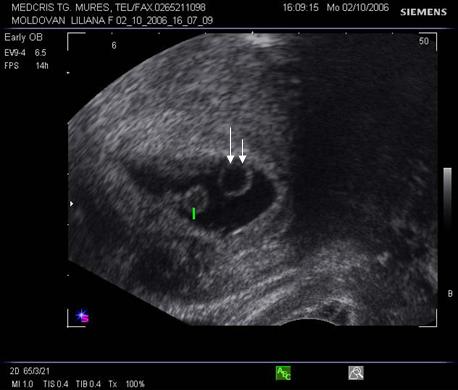

Fig nr 40 .

Sarcina 5 sapt monoamniotica, cu doua vezicule viteline si un embrion (cu o

sageata ). Vezicula vitelina normala ca marime ( cu linie ) apartine embrionului vizibil. Vezicula

vitelina anormal de mare ( cu doua sageti ) si fara embrion indica o sarcina

gemelara , cu lipsa dezvoltarii unui

embrion